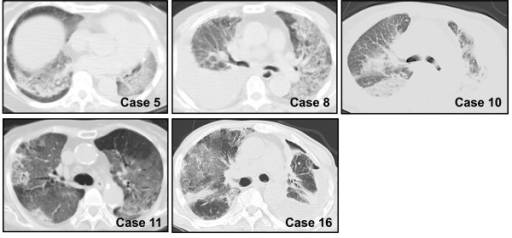

Rapid progression from initial symptoms to respiratory failure is a key feature. An X-ray that shows ARDS is necessary for diagnosis (fluid in the small air sacs (alveoli) in both lungs). In addition, a biopsy of the lung that shows organizing diffuse alveolar damage is required for diagnosis. This type of alveolar damage can be attributed to nonconcentrated and nonlocalized alveoli damage, marked alveolar septal edema with inflammatory cell infiltration, fibroblast proliferation, occasional hyaline membranes, and thickening of the alveolar walls. The septa are lined with atypical, hyperplastic type II pneumocytes, thus leading to the collapse of airspaces. Other diagnostic tests are useful in excluding other similar conditions, but history, X-ray, and biopsy are essential. These other tests may include basic blood work, blood cultures, and bronchoalveolar lavage.[citation needed] The clinical picture is similar to ARDS, but AIP differs from ARDS in that the cause for AIP is not known.